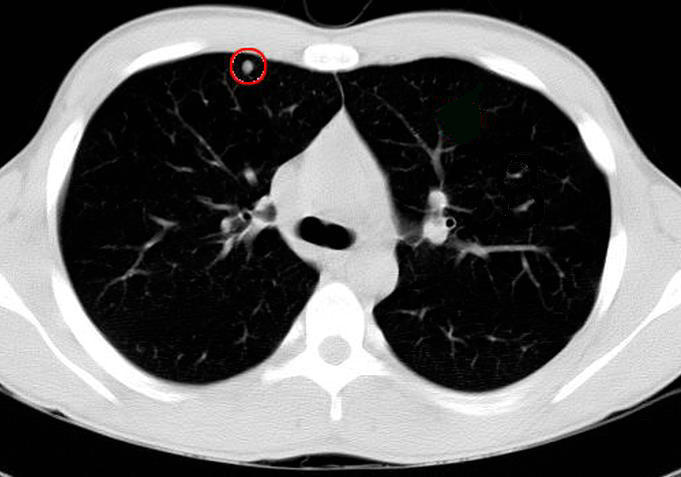

第一种,磨玻璃结节(gross glass nodule, ggn),或者磨玻璃阴影

而根据影像学显示的结节密度可将肺部小结节分类如下:_ 纯磨玻璃结节(pggo):均匀的磨砂状阴影,恶性概率为18%.

4.直接手术 随着胸部ct的普及,越来越多的人发现有肺部结节,对于6-10mm的肺结节,由于结节太小,肺穿刺几乎是穿不到的,根据ct中结节形态、位置、ct值,比如磨玻璃结节或者混合磨玻璃结节等高度怀疑肺癌时,可以直接手术治疗.